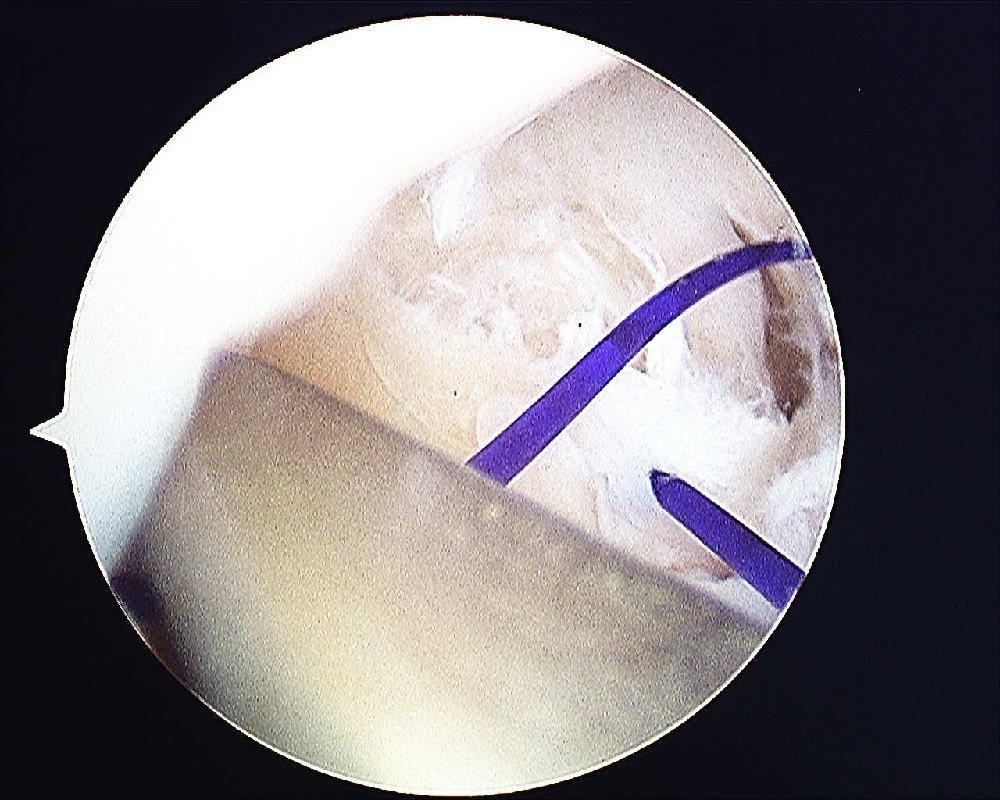

The cannula is passed into the joint again to pass a suture shuttle. I use the PDS 3/0 as a suture shuttle.

The 1st PDS suture that was passed through the TFCC is shuttled back into the joint and out of the capsule.